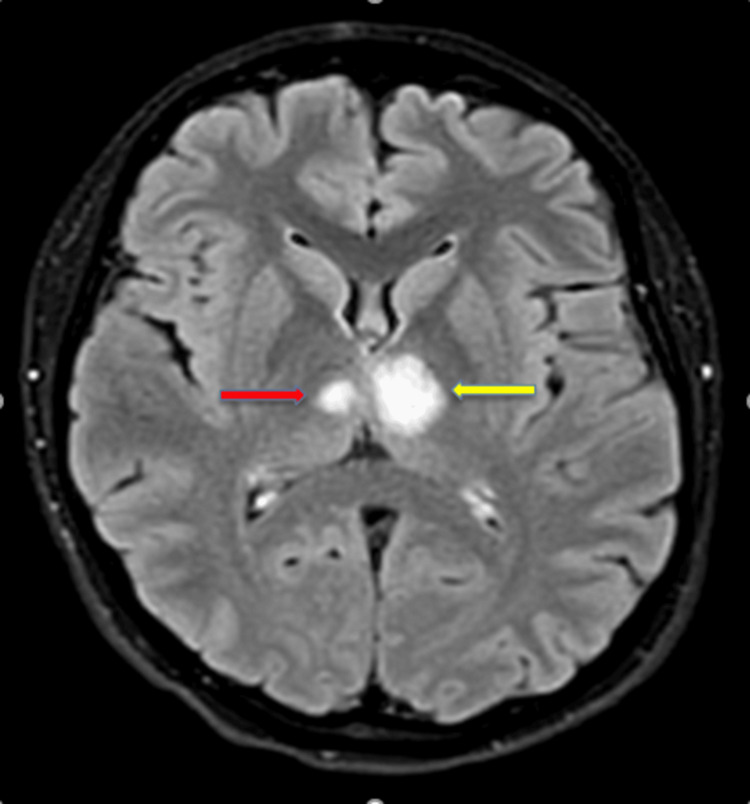

Excellent presentation by @PereraKanjana 👏🏻👏🏻 Aproach to ESUS workup ✅️ CTA is superior to MRA (prone to artifatcs) ✅️ TEE/TCD with microbubbles in the young ✅️ Prolonged cardiac monitoring - older patients #ISC26 @StrokeAHA_ASA

🧑‍🌾Young, previously healthy adult with sudden confusion, hypersomnolence, memory impairment and blurred vision. No fever, no metabolic abnormalities, no focal motor deficit. Initial workup is unrevealing. 👨‍⚕️What’s your leading diagnosis?